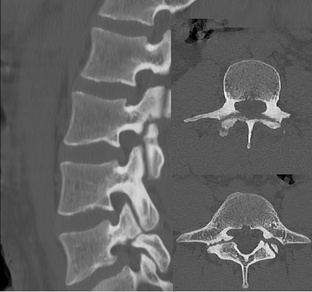

Листез, спондилолистез истинный - смещение тела вышележащего позвонка по отношению к нижележащему. Псевдолистез - проседание тела вышележащего позвонка по отношению к нижележащему. Спондилолиз - врожденный или приобретенный дефект – разрыв в области дужек позвонка разделяющий позвонок на две части.

Листез, спондилолистез - смещение тела вышележащего позвонка по отношению к нижележащему. При таком смещении есть несовпадение переднего и заднего контура тела позвонка вышележащего по отношению к нижележащему. Рентгенограмма истинного листеза: Схематичное изображение истинного листеза: Псевдолистез - проседание тела вышележащего позвонка по отношению к нижележащему. При...